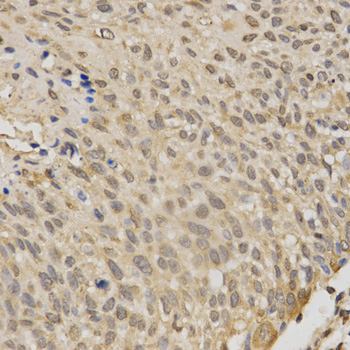

Immunohistochemistry of paraffin-embedded human esophageal cancer using STK11 antibody at dilution of 1:200 (x400 lens)